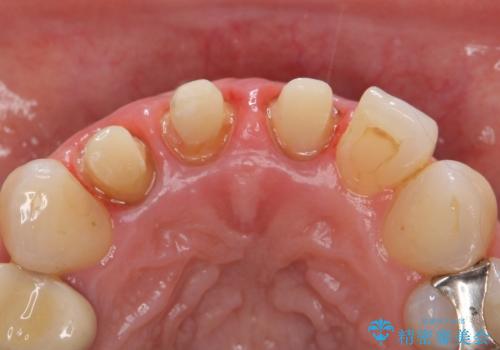

- 前歯の長さが違うのが気になるといらっしゃった方の症例です。

根尖病変を認めたため再根管治療を行った後、オールセラミッククラウン(スペシャル)にて補綴を行いました。

- オールセラミッククラウン(スペシャル)…¥130,000×3、仮歯…¥10,000×3、ファイバーコア…¥20,000×3費用は治療当時の料金となります